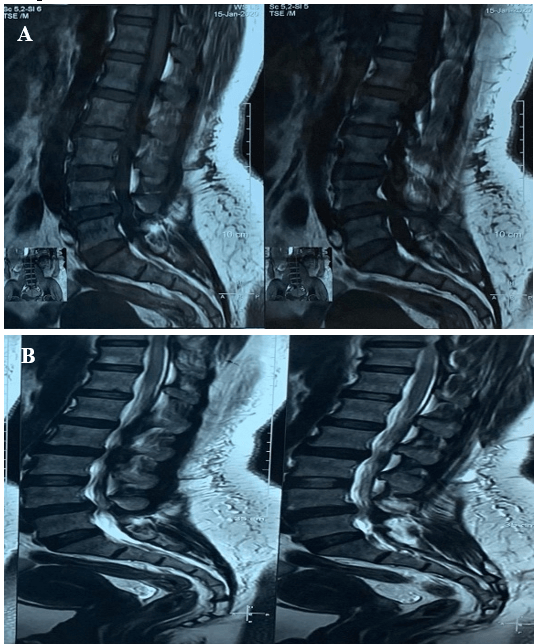

A 45-year-old female was presented with the complaints of low backache with sciatica for 4 years. The pain increased on walking and relieved by taking rest. She was nondiabetic and normotensive. On examination there was a weakness in both extensors of the toes; SLR, Deep tendon reflexes were normal. She had dysaesthesia on both L5 dermatomes. MRI of LS Spine (Figure 1) revealed a prolapsed disc at L4/5. On dynamic X-ray, LS spine revealed grade 1 spondylolisthesis (L4 over L5) (Figures 2 & 3). The patient was subjected to decompression, stabilization at L4 and L5 by pedicle screw, with L4/5 fusion. The post-operative period was uneventful, and she was well recovered. Patient follow-up was conducted periodically. She was relieved of symptoms after 2 years of follow-up, with a complete range of spine motion.

Figure 1: A) & B) MRI of Lumbosacral spine sagittal view showing disc bulge at L4/5 level.

In the current study, the patient had a history of low back pain alongside sciatica and dysaesthesia on both L5 dermatomes. Maurer et al. reported that of the 22 asymptomatic juvenile rowers in their study, 5 demonstrated the high signal intensity of the pars interarticularis on T2-weighted MRI scans, and none showed manifestations related with spinal issues as long as 3 months after the end of the study [13]. For this current study, MRI of LS Spine revealed a prolapsed disc at L4/5. On dynamic X-ray, LS spine revealed grade 1 spondylolisthesis (L4 over L5). The MRI permitted the identification of dynamic degenerative spondylolisthesis, consistent with the clinical picture. Utilizing MRI, we had the option to show that the marvel of instability in spondylolisthesis does happen and that pathologic highlights may show more plainly under stacking. This finding may suggest it as a radiographic help with continuing with surgical decompression.